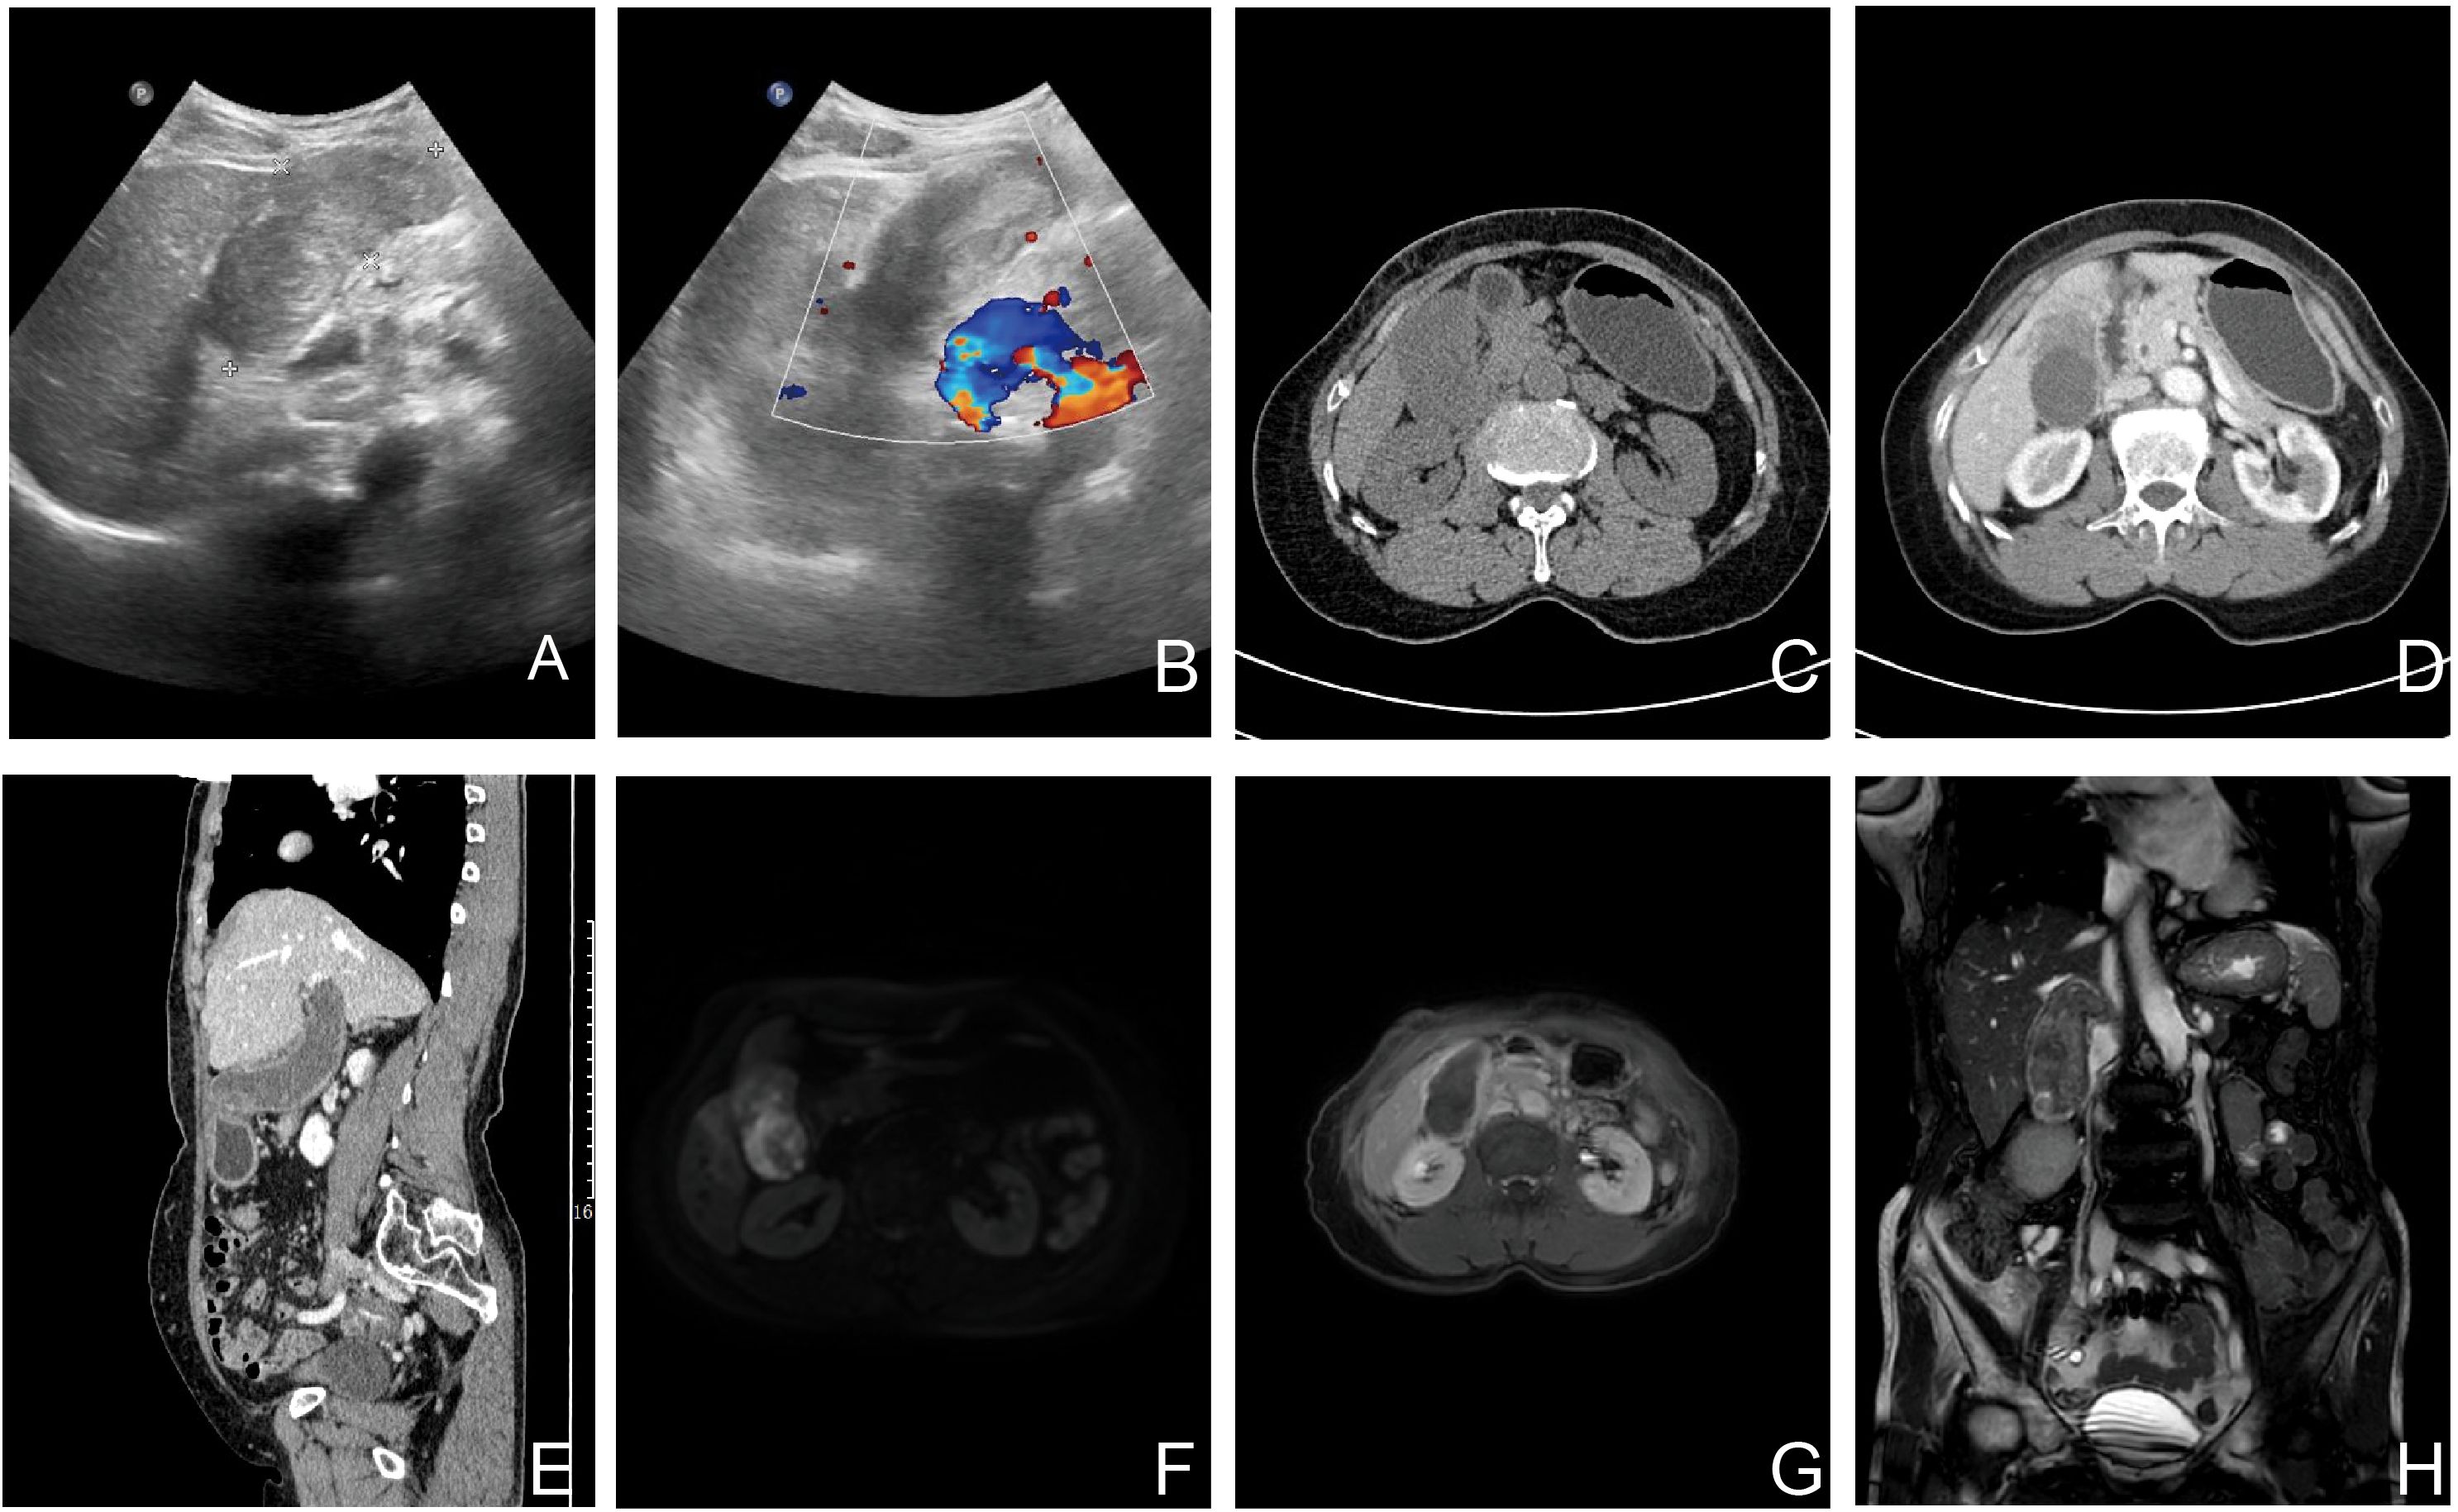

Gallbladder carcinosarcoma (GBCS) is indeed an exceptionally rare and aggressive malignancy, accounting for less than 1% of all primary gallbladder tumors. This tumor is characterized by the presence of both carcinomatous (epithelial) and sarcomatous (mesenchymal) components, making it a unique and diagnostically challenging entity. Herein, we report a case of a 71-year-old female patient who presented with a one-year history of vague epigastric pain. AFP levels were markedly elevated. Preoperative imaging revealed gallbladder enlargement with heterogeneous contrast enhancement, raising suspicion of malignancy. The patient subsequently underwent radical cholecystectomy, and postoperative histopathological examination confirmed the diagnosis of GBCS with osteosarcomatous differentiation. The patient has since completed her first cycle of chemotherapy. Even with radical resection and adjuvant chemotherapy, GBCS carries a grave prognosis. Heightened clinical suspicion, thorough imaging assessment, and confirmatory histopathological biopsy are essential for accurate preoperative diagnosis. Surgical optimization and personalized treatment strategies remain critical to improving outcomes.